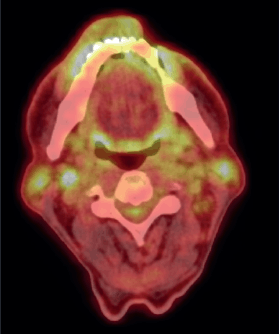

Figure 3. Post-chemotherapy PET CT scan, showing FDG avid residual left lower lip lesion.

After a thorough discussion in the multidisciplinary lymphoma tumour board, the patient was started on a chemotherapy regimen consisting of Cyclophosphamide 750 mg/m² IV on day 1, Doxorubicin 50 mg/m² IV on day 1, Vincristine 1.4 mg/m² (max 2 mg) IV on day 1, Etoposide 100 mg/m² IV on days 1–3 and Prednisone 100 mg PO on days 1–5, administered over 6 cycles every 3 weeks. This regimen was well-tolerated by the patient. Interim PET scan was repeated after 4 cycles of chemotherapy, which showed complete metabolic response (Deauville 3). After the completion of six cycles, an end-of-treatment PET-CT was done, which revealed complete metabolic response (Deauville 3) with mild FDG-avidity over lip lesion and complete resolution of the FDG-avid lymph nodes (Figure 4).